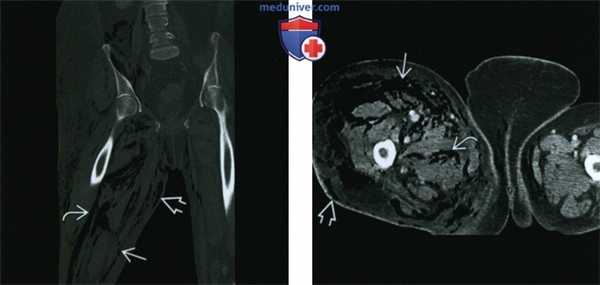

(Слева) КТ, фронтальный срез, у пациента 54 лет с сахарным диабетом и пузырно-тонкокишечным свищем, вследствие быстрого ухудшения визуализируются расслоение воздухом тканей подкожной клетчатки, поверхностной и глубокой фасции. Происходит распространение в забрюшинное пространство по фасциальному футляру подвздошно-поясничной мышцы.

(Справа) Аксиальный КТ срез у этого же пациента: воздух, расслаивающий ткани подкожной клетчатки, поверхностной и глубокой фасции. В этом случае некротизирующего фасциита в процесс вовлечены промежность и противоположное бедро.